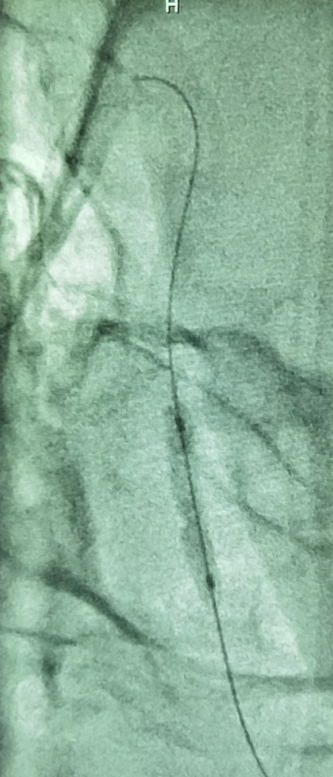

选择Neuroform EZ 3.5X20mm支架植入,术后工作角度造影如下:

术后标准正侧位。

患者醒麻醉后无新增不适,4天后步行出院。